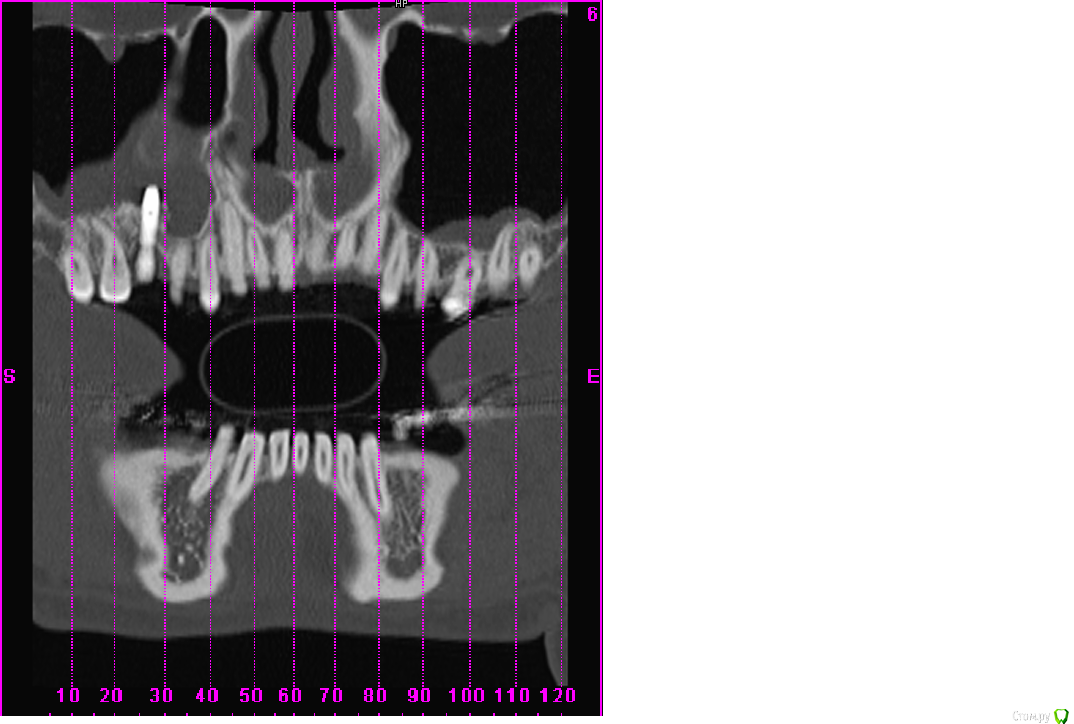

scrappy_coco Опубликовано 17 февраля, 2015 Поделиться Опубликовано 17 февраля, 2015 (изменено) Здравствуйте! После синус-лифтинга и костной пластики был установлен имплантат 6 зуб(6месяцев назад, настал момент протезирования, зашаталась 5ка рядом с имплантом, встал вопрос о удалении и имплантировании 5ки, всвязи со смещением и более этетичным видом сразу двух изготовленный коронок)решил проконсультироваться с другими врачами, которые диагностировали ассептический гайморит, нужно удалять имплантат, мой врач говорит, что все нормально, утолщение слизистой- результат манипуляций с областью, гайморит в состоянии ремиссии ) . Симптоматики гайморита нет. Кто прав? Рассмотрите, пожалуйста, ситуацию в прилагающихся скринах . Изменено 17 февраля, 2015 пользователем scrappy_coco Ссылка на комментарий

Mane Опубликовано 17 февраля, 2015 Поделиться Опубликовано 17 февраля, 2015 (изменено) Гайморита нет Изменено 17 февраля, 2015 пользователем Mane Ссылка на комментарий

scrappy_coco Опубликовано 20 февраля, 2015 Автор Поделиться Опубликовано 20 февраля, 2015 Гайморита нетимеет ли данная конструкция перспективу, не разовьется ли гайморит в последствии при нагрузке Ссылка на комментарий

Mane Опубликовано 22 февраля, 2015 Поделиться Опубликовано 22 февраля, 2015 имеет ли данная конструкция перспективу, не разовьется ли гайморит в последствии при нагрузкеОртопедическая конструкция при адекватной гигиене к гаймориту не приведет. Удалить 15 - глупость. Компромисная эстетика - это если приоочить зубы 17 и 15 с контактных сторон и сделать в этих условиях коронку на имплант. Идеальный план:Планирование ортодонтического леченияВозможно удаление имплантаОртодонтич дечениеВозможно новая имплантацияПротезирование Ссылка на комментарий